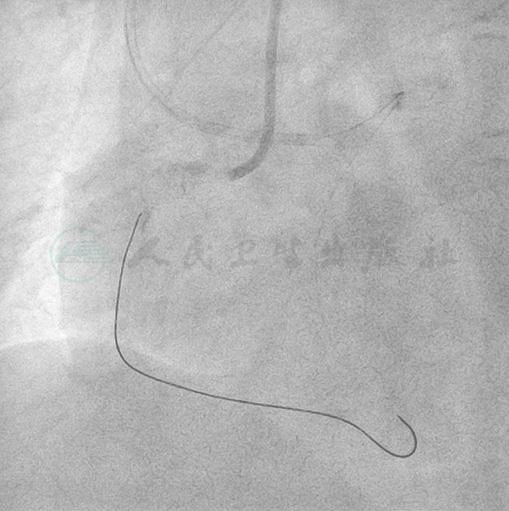

1周后再次尝试处理RCA病变,同样采取左右桡动脉途径,经右桡动脉置入6F EBU3.5指引导管(90cm)准备尝试经前降支-间隔支路径逆向开通RCA病变(图5、图6)。先使用Runthrough NS导丝将Finecross微导管(150cm)引入第一间隔支,其中段至远端连接部呈多个Z形小折弯,通过困难(图7、图8)。在微导管前端注射造影指导下,交叉使用SION、Field FC、Hypercoat Runthrough导丝,逐渐推送微导管到达后降支并至RCA闭塞段以远(图9~图12)。

图5 右桡动脉选择EBU3.5指引导管,尝试前降支-间隔支途径逆向技术开通右冠

图6 第一间隔支粗大侧支发育良好,但远端连接部见多个折弯串联